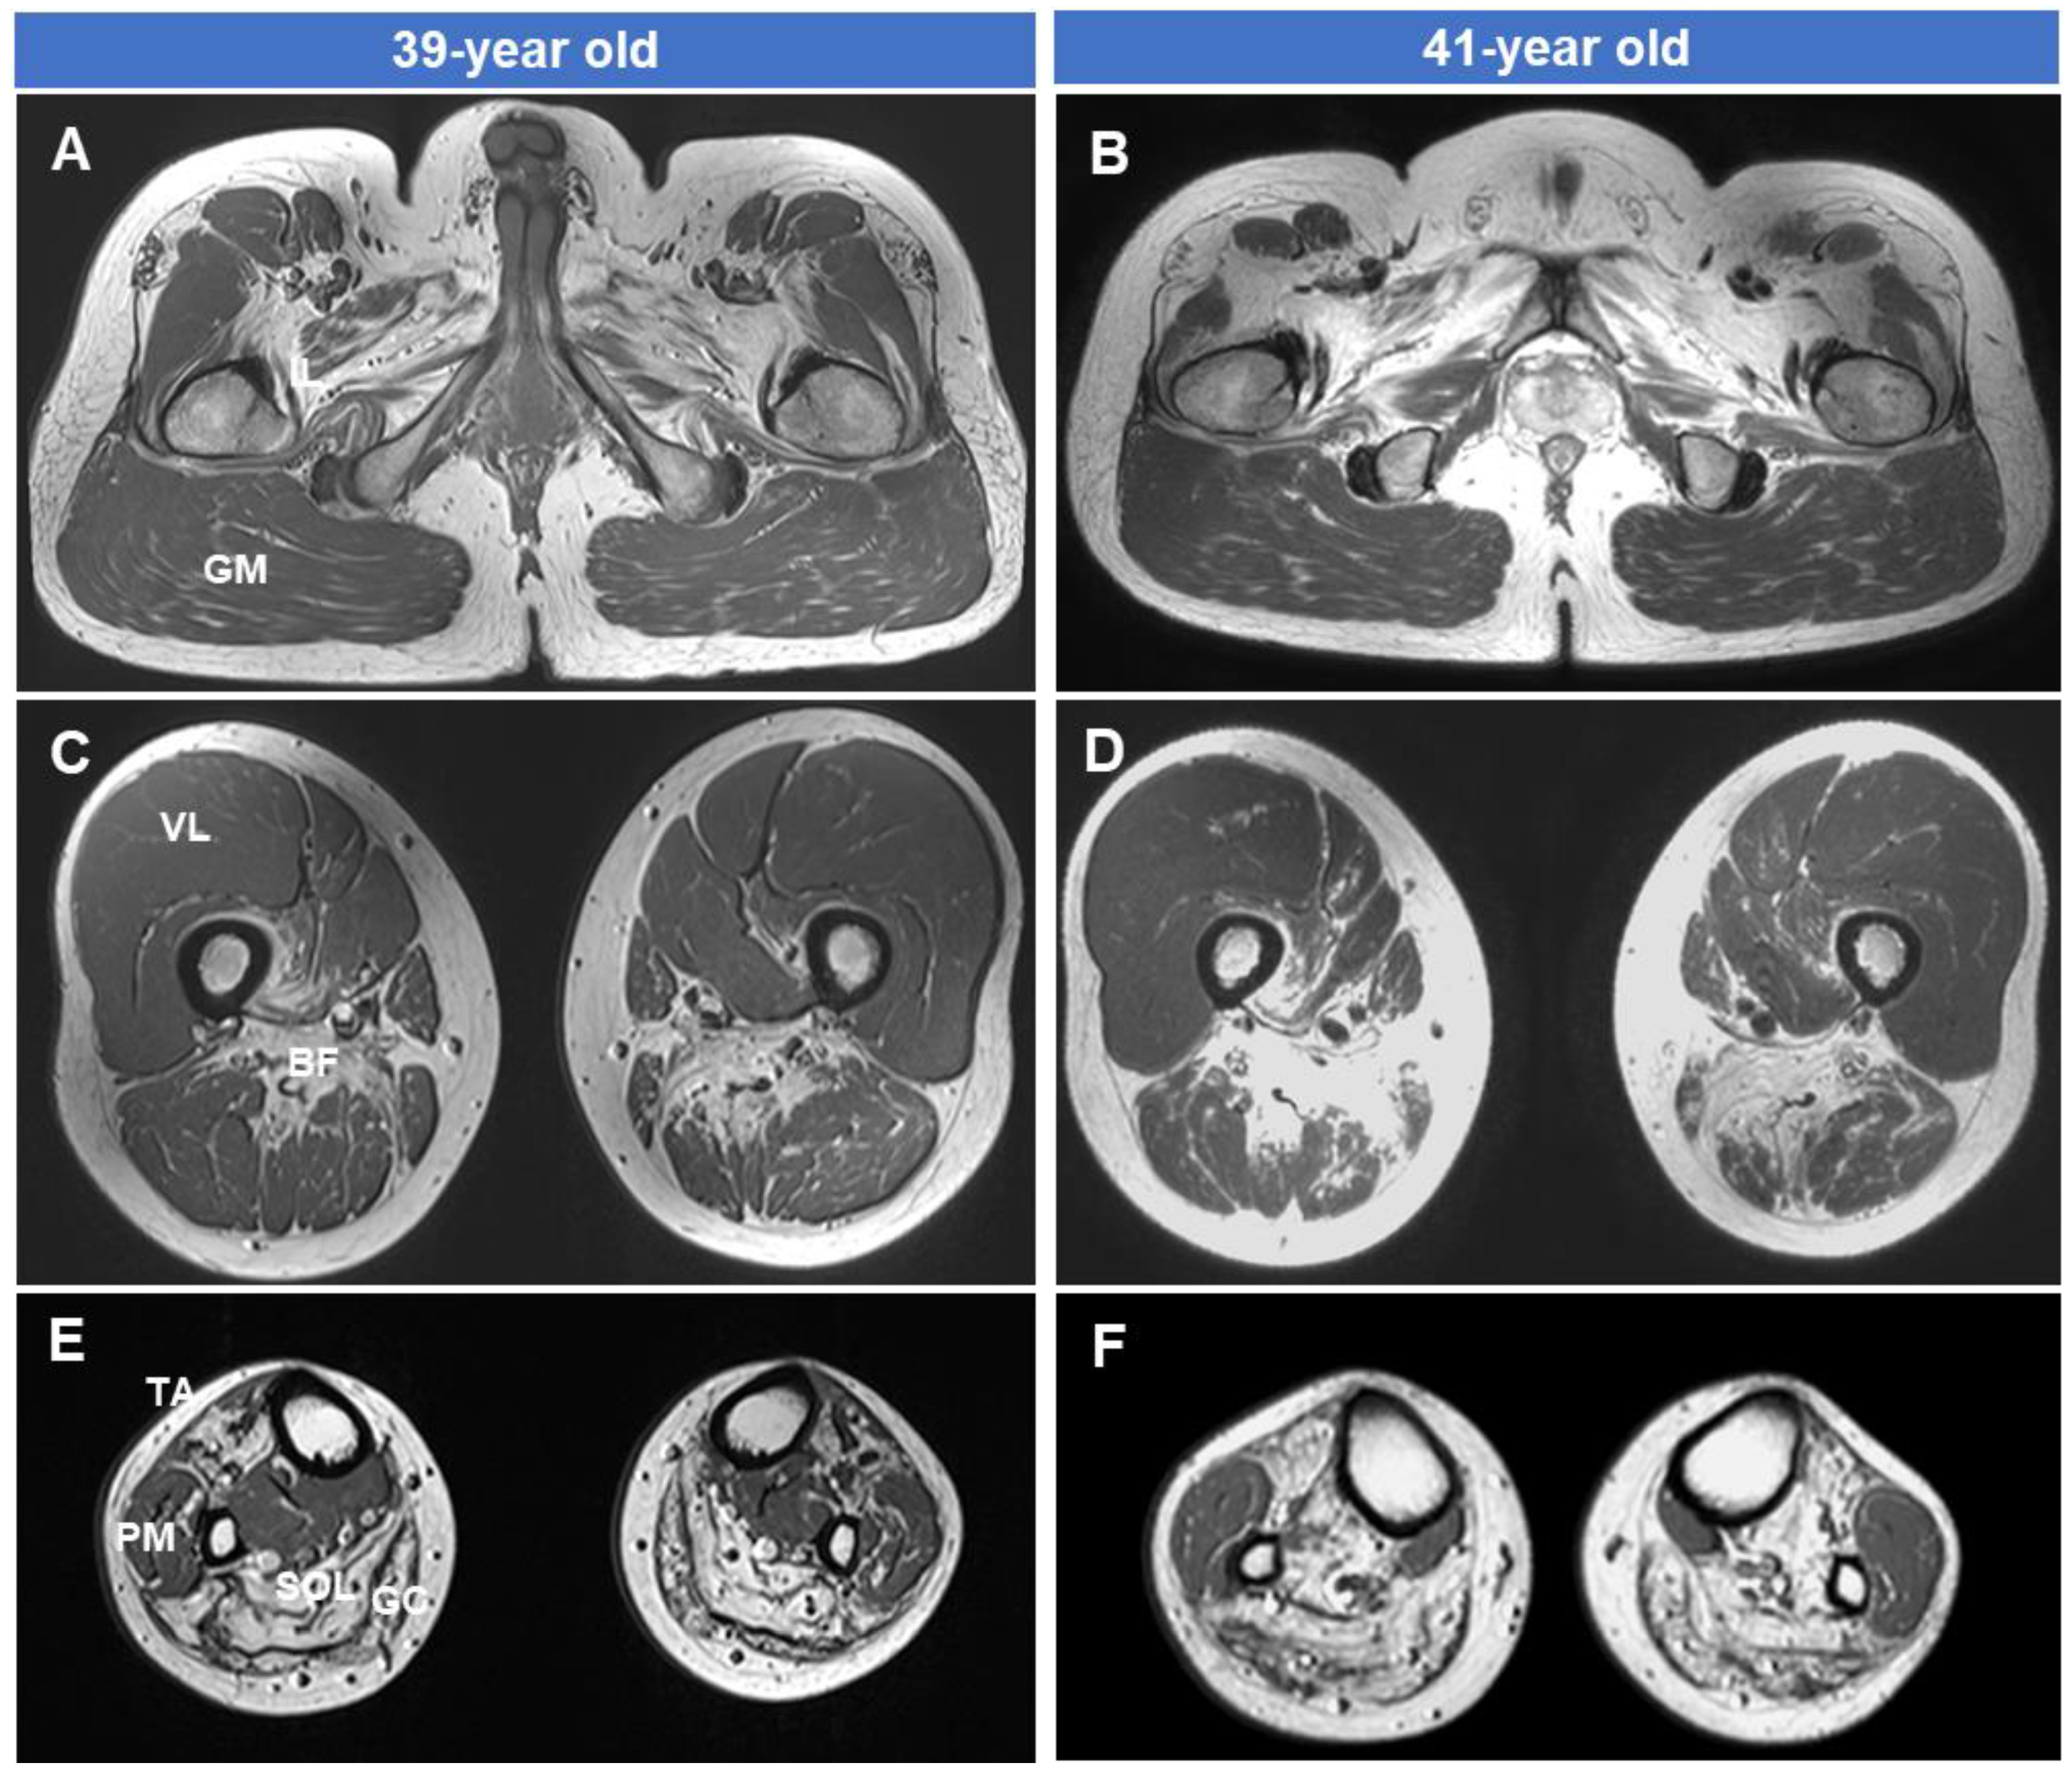

3.4. Fatty Replacements of Lower Extremity Muscles